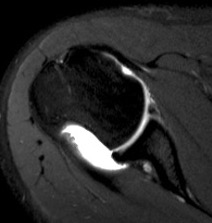

Engaging / Large Hill Sachs lesion

Filling Hill Sachs defect with infraspinatus / posterior capsule